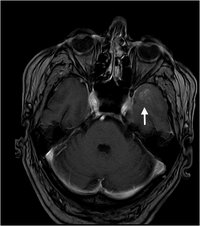

Limbische Enzephalitis

Limbische Enzephalitis - T2

Hyperintensität hippocampal und parahippocampal